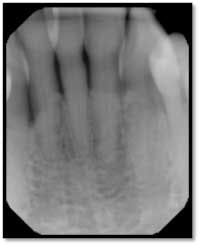

LR Pre TxPockets: 4-8mm

Severe bone loss #26, 8mm DF, 5mm straight facial, +2 mobility